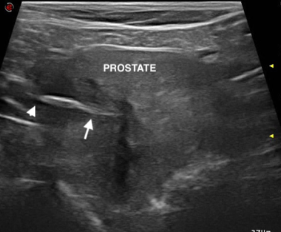

논문이 아직 열리지 않아 내용은 모르겠고 방광에서 발견된 풀씨 케이스의 초음파 사진이니 참고하기 바람